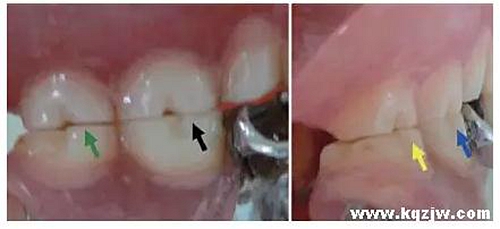

其包括①頰舌面塑形,以改善上下牙的覆(牙合)覆蓋關(guān)系(圖8);②近遠(yuǎn)中向塑形,以改善鄰接關(guān)系或外展隙形態(tài)(圖9)。

①形成一定的溝窩結(jié)構(gòu),例如頰溝、舌溝,以改善食物溢出通道;②消除銳邊、銳緣、銳棱等異常磨耗所形成的微小結(jié)果(圖10)。

通過調(diào)改咬合紙檢測所顯示的咬合接觸點(diǎn),將正中咬合時(shí)的接觸引導(dǎo)到支持尖牙尖壁上,其中下頜后牙以頰尖舌斜面為主,上頜后牙以舌尖頰斜面為主(圖11)。盡量使咬合接觸點(diǎn)廣泛分布,力度(著色程度)均衡。